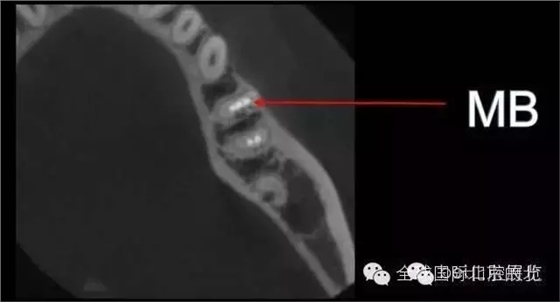

DB,DL.根管充填完成,樹脂封閉根管口,繼續(xù)探索未知的近中隱藏根管,所以決定拍1/4 CBCT確認MB存在, 其實預備的是MM和ML,

證實確實是遺漏了MB,

終于完成根充

MM,ML其實融合為一個根管口的,截面就是三根管的形態(tài),然后做了一個簡單清晰的三維重建,形態(tài)還是挺不錯的 。 一個月后復查,如果無明顯反應就進行及時的冠修復,做好冠方封閉 以后3-6個月再做跟蹤回訪